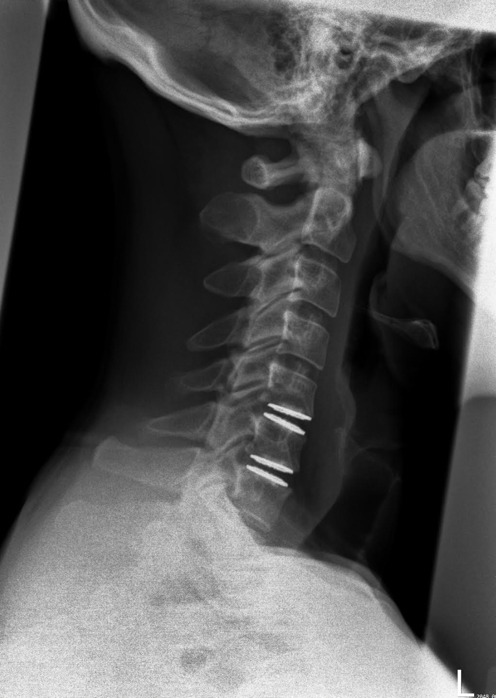

The subject was seen in PT for 14 sessions spanning 16 weeks. The initial evaluation session was one hour long and follow up sessions were 30 minutes in length. PT interventions included manual therapy (soft tissue and joint mobilization), therapeutic exercise (targeting cervical spine, thoracic spine and upper extremity to address mobility and strength), and weightlifting body mechanics education. Radiographic confirmation of prosthesis placement and healing was monitored at postoperative weeks six and 12 (Figures 4-5).

Improvements were noted with NDI (14% to 0%), PSFS (3.4/10 to 10/10), SF-12 PCS (+5.4) and SF-12 MCS (+25.7), and NPRS (2/10 to 0/10). Cervical AROM improved in extension 55-60 degrees, total rotation 60-75 degrees, total lateral flexion 20-45 degrees, and DNF endurance 5-35 seconds. Postoperative radiographs at week 6-12 no evidence of prosthesis malpositioning, displacement, subsidence or heterotopic ossification.